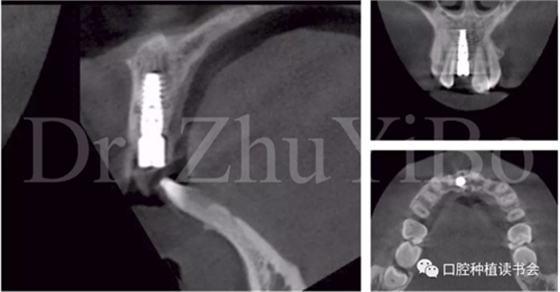

術(shù)前cbct顯示:右上中切牙牙根牙槽突類型為一型(圖8)。牙齦為厚型牙齦類型;咬合關(guān)系基本正常。

圖8 CBCT:11可見明顯根折線,無法保留

4.2.3 植入Nobel active種植系統(tǒng) RP 13mm種植體,植入扭矩大于45Ncm,初期穩(wěn)定性良好(圖11、圖12))。

圖15術(shù)后即刻CBCT示:種植體軸向及深度良好